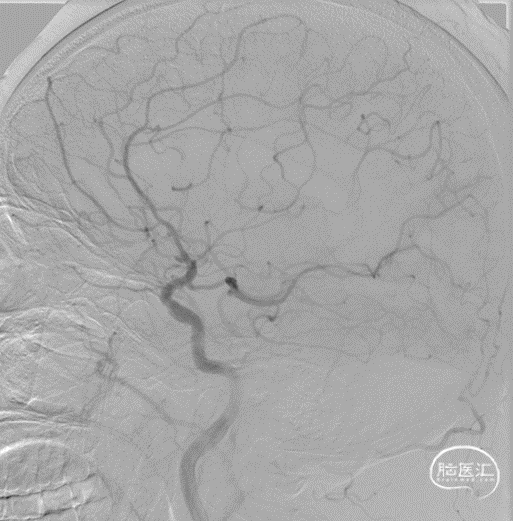

脑血管造影:右侧大脑中动脉M1段闭塞,代偿不足。

选取工作角度造影,测量病变长度。

最后工作位造影和正侧位造影,右侧大脑中动脉区域血流恢复,灌注满意。